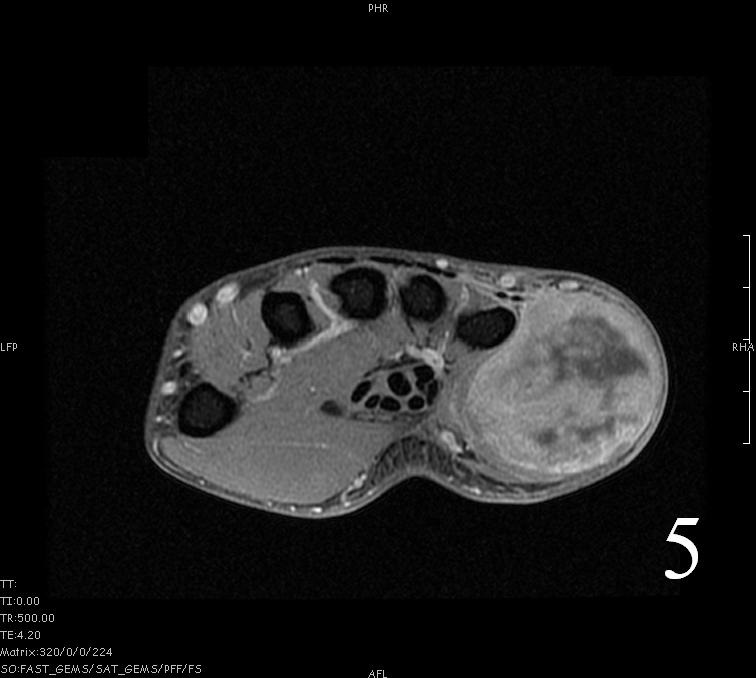

MRI

- Heterogeneous mass (does not follow signal of skeletal muscle)

- Isointense to skeletal muscle on T1 (Fig. 4, Fig. 5, Fig. 7, Fig. 8)

Fig. 4-9: MRI of a rhabdomyosarcoma of the hand. The MRI is nonspecific and shows a heterogeneous mass particularly on postgadolinium images T1 W images (Fig. 8) and T2 W images (Fig. 9).